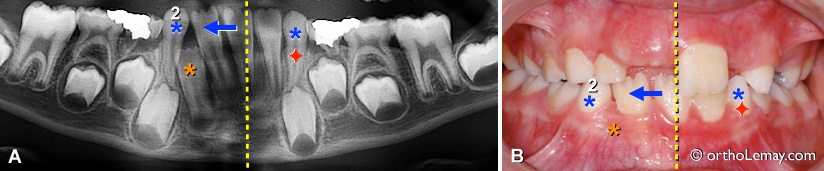

Dans d’autres cas, comme celui illustré ci-dessus, il peut y avoir asymétrie dans la position des incisives sans qu’une canine ne soit tombée.

(A, B) Les incisives se sont déplacées vers la droite (flèche) de la ligne médiane (pointillé jaune) et une latérale inférieure (*orange) est bloquée et ne peut sortir par manque d’espace .

Il serait alors indiqué d’extraire la canine non du côté où il manque d’espace (droite du patient) mais du côté opposé (gauche) (* bleu = canines temporaires, losange rouge = canine à extraire). Extraire la canine droite ne ferait qu’augmenter la tendance qu’ont les incisives à migrer vers la droite en leur donnant plus d’espace.

Après un délai de ± 12 mois, l’autre canine (* bleu 2) pourra être extraite. Il est possible qu’après un tel délai la position des incisives se soit améliorée un peu sans aucune autre intervention.